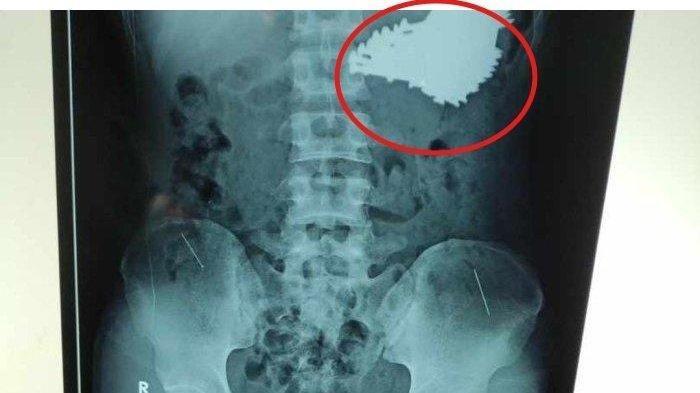

Saat dibawa berobat ke RSUD Indramayu, tim medis dibuat terkejut karena menemukan 70 butir paku berukuran 4-7 centimeter bersarang di lambung SH dari hasil foto rontgen.

SH saat ini sudah menjalani operasi, tim medis pun berhasil mengeluarkan 70 paku tersebut dalam operasi yang berlangsung selama kurang lebih 2 jam.